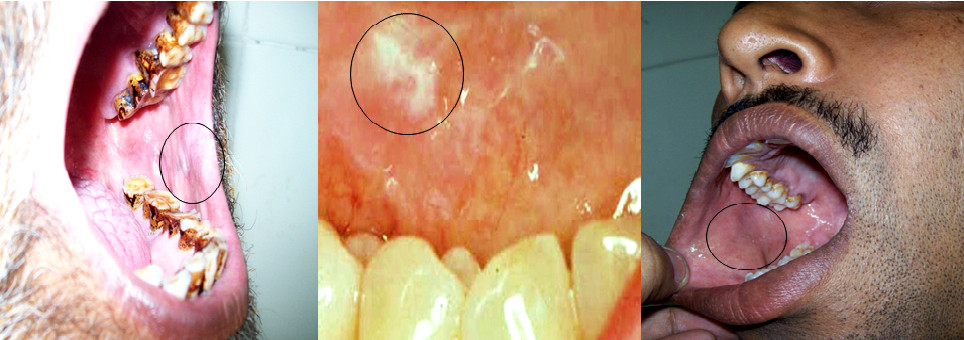

In patients with discrepant oral brush biopsy and scalpel biopsy results, we confirmed the presence of the brush biopsy tissue defect in the histological specimen of the scalpel biopsy. This ensured that the same part of the lesion was indeed sampled by both the brush and the scalpel instruments. (Figure 2)

Figure 2. Histopathologic specimen demonstrating the oral biopsy defect sampling the entire thickness of the epithelium.

(H &E x100).